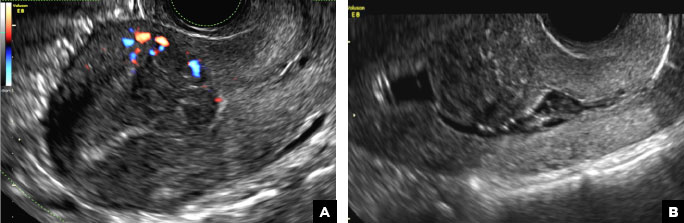

B) Submucosal fibroid CORRECT

Submucosal fibroids on ultrasonography appear as heterogeneous hypoechoic lesions distorting the endometrial cavity.1 In contrast to endometrial polyps, which involve the endometrium only, submucosal (intracavitary) fibroids originate in the myometrium, as clarified in Figures 3A & B. SHG demonstrates a broad-based mixed hypoechoic/isoechoic lesion protruding into the endometrial canal but preserving the echogenic endometrium, distinguishing myometrial from endometrial lesions. Submucosal fibroids often distort the endometrial myometrial interface and demonstrate acoustic shadowing.2,3

Submucosal fibroid. (A) Transvaginal pelvic ultrasound with color Doppler demonstrates a heterogeneous hypoechoic/isoechoic lesion arising from the myometrium (long arrow) and distorting the endometrial cavity. (B) SHG demonstrates a broad-based hypoechoic lesion protruding into the endometrial canal with areas of acoustic shadowing (arrowhead) but preserving the echogenic endometrium (short arrow).